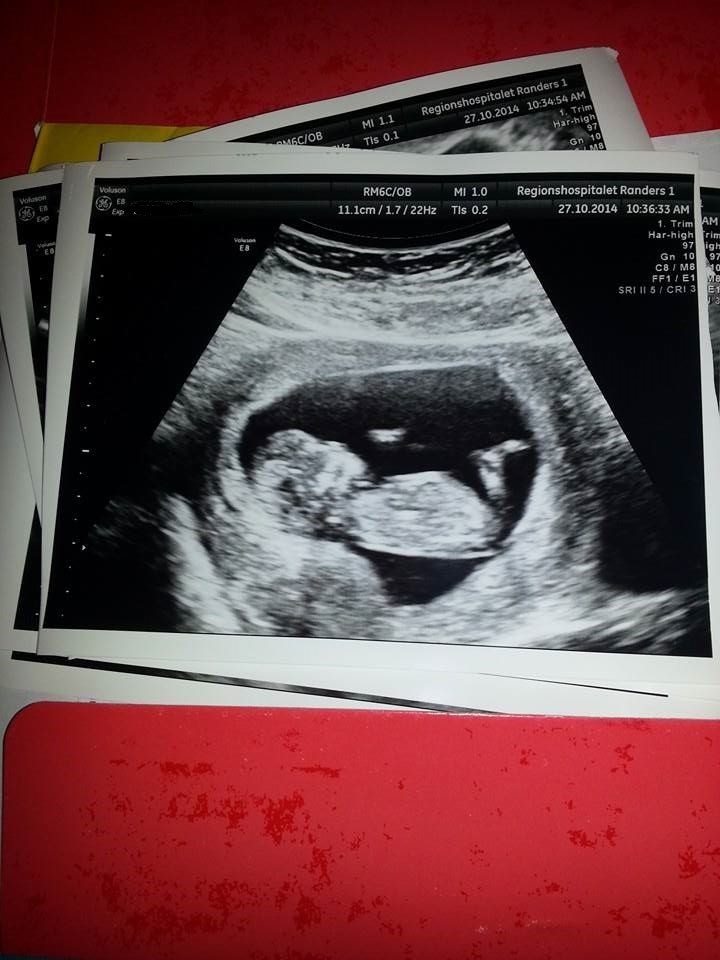

Den smukkeste baby i mine øjne.

Another Chance skriver: Var til nakkefolds scanning i dag og hørte den mest fantastiske hjerte lyd og så mit lille barn på skærmen strække sig og posere for os, jeg kunne virkelig ikke holde mine tåre tilbage. Er en meget lykkelig kommende singlemor, da jeg har valgt at få en anonym donor til at være far til mit barn, på en privat klinik i Hobro (Gaia) så godt ske at jeg ikke har nogen at dele dette med i min hverdag, men den lille baby vil blive så elsket alligevel. Er i uge 12+2 og terminen blev beregnet til d. 9 maj 2015 Har faktisk ingen spørgsmål eller noget, ville bare dele min lykke

Er i uge 12+2 og terminen blev beregnet til d. 9 maj 2015